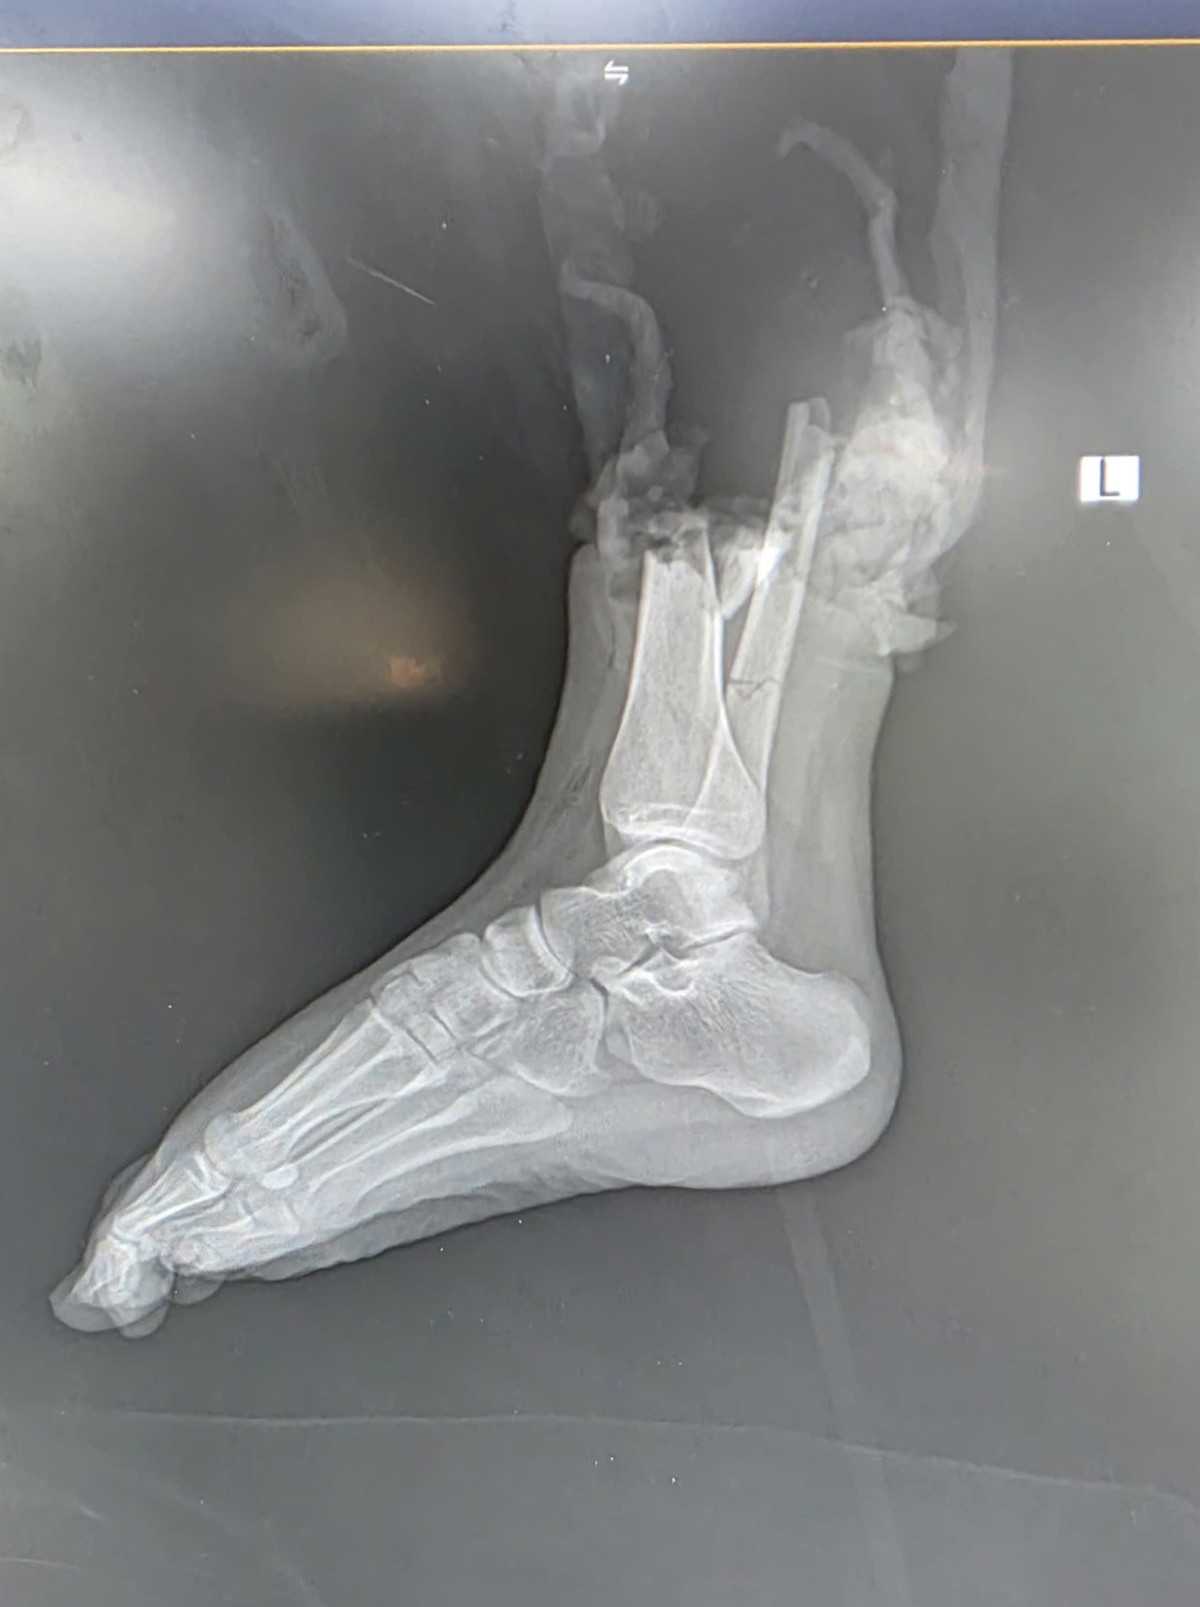

Vụ việc xảy ra vào khuya ngày 15/10, tại phố Trịnh Văn Bô (quận Nam Từ Liêm, Hà Nội), gần khu vực Trường Cao đẳng FPT Polytechnic. Sau cú va chạm mạnh giữa mô tô phân khối lớn và xe máy, nữ sinh Đ.P. (19 tuổi, quê Bắc Ninh) - người điều khiển xe máy bị đứt lìa ở vị trí phức tạp - 1/3 dưới cẳng chân phải, kèm dập nát phần mềm.

Hình ảnh tổn thương trên CT - Ảnh BVCC

Ngay sau tai nạn, nạn nhân được sơ cứu và chuyển khẩn cấp tới Bệnh viện TWQĐ 108 trong “thời gian vàng” - khoảng 2 giờ sau chấn thương. Ngay trong đêm khuya, kíp y bác sĩ đã nhanh chóng tiến hành cắt lọc, xử lý tổn thương, nối mạch máu, thần kinh, gân cơ và xương.

Sau hơn 6 giờ phẫu thuật căng thẳng, phần chi thể đứt rời được nối thành công. Sau phẫu thuật gần 2 tuần, bệnh nhân đã khỏe mạnh và có thể cử động được các ngón chân, cho thấy kết quả phục hồi khả quan.